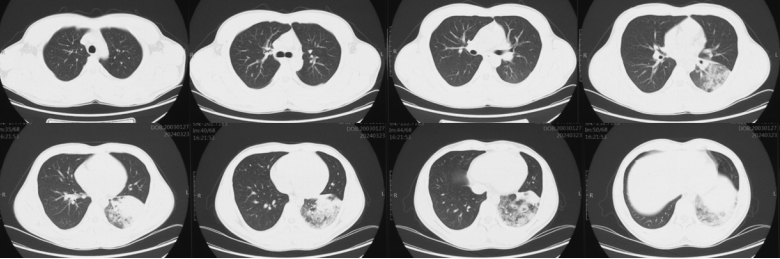

2012年北京朝阳医院的研究对487例社区获得性肺炎(CAP)患者中的18例经实验室确诊的腺病毒重症社区获得性肺炎(SCAP)进行PCR病毒分型,结果均为B型腺病毒,AdV-11、7、3和14型较常见,其中AdV-11型最常见(10/17)。患者临床表现为流感样症状,在发病后6天出现气短或严重呼吸困难。ARDS患者常表现为呼吸困难、血清肌酶升高、影像学双侧多发实变、斑片状或磨玻璃样渗出影。55%应用激素治疗,病死率为11%。其中一例23岁男性因腺病毒引起ARDS,X线胸片显示:发病后第3天双下肺致密片状浸润影(图13A)起病后第5天加重(图13B)起病后第7天右肺及左下肺出现致密实变,左肺上叶尚未明显受累(图13C)第9天双肺广泛实变,呈ARDS改变(图13D)

图片

图13  腺病毒引起的ARDS影像学表现